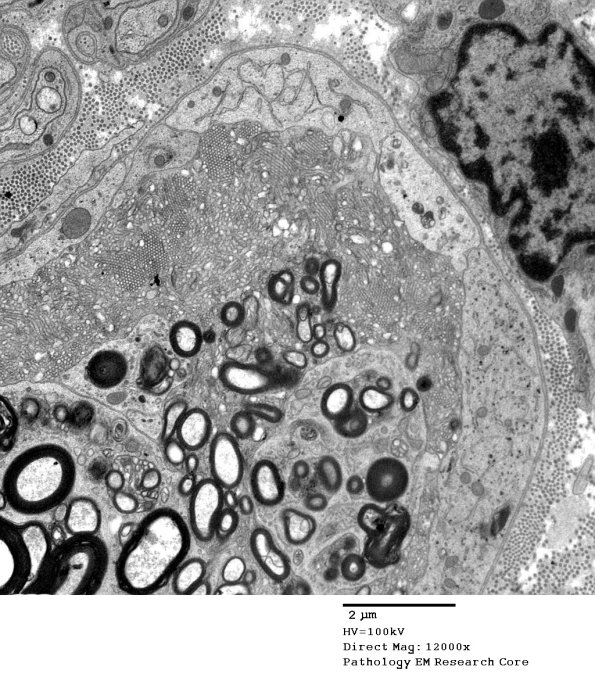

Washington University Experience | PERIPHERAL NEUROPATHY | 4 AXONAL DEGENERATION | 3 Electron Microscopy | 2G3 Axonal Degeneration (Case 7) EM 017A - Copy

2G3-5 In this region there are vesicular myelin changes and adjacent Schwann cell processes which may resemble axons. Ribosomes in Schwann cell processes often give a hint they are not axons.